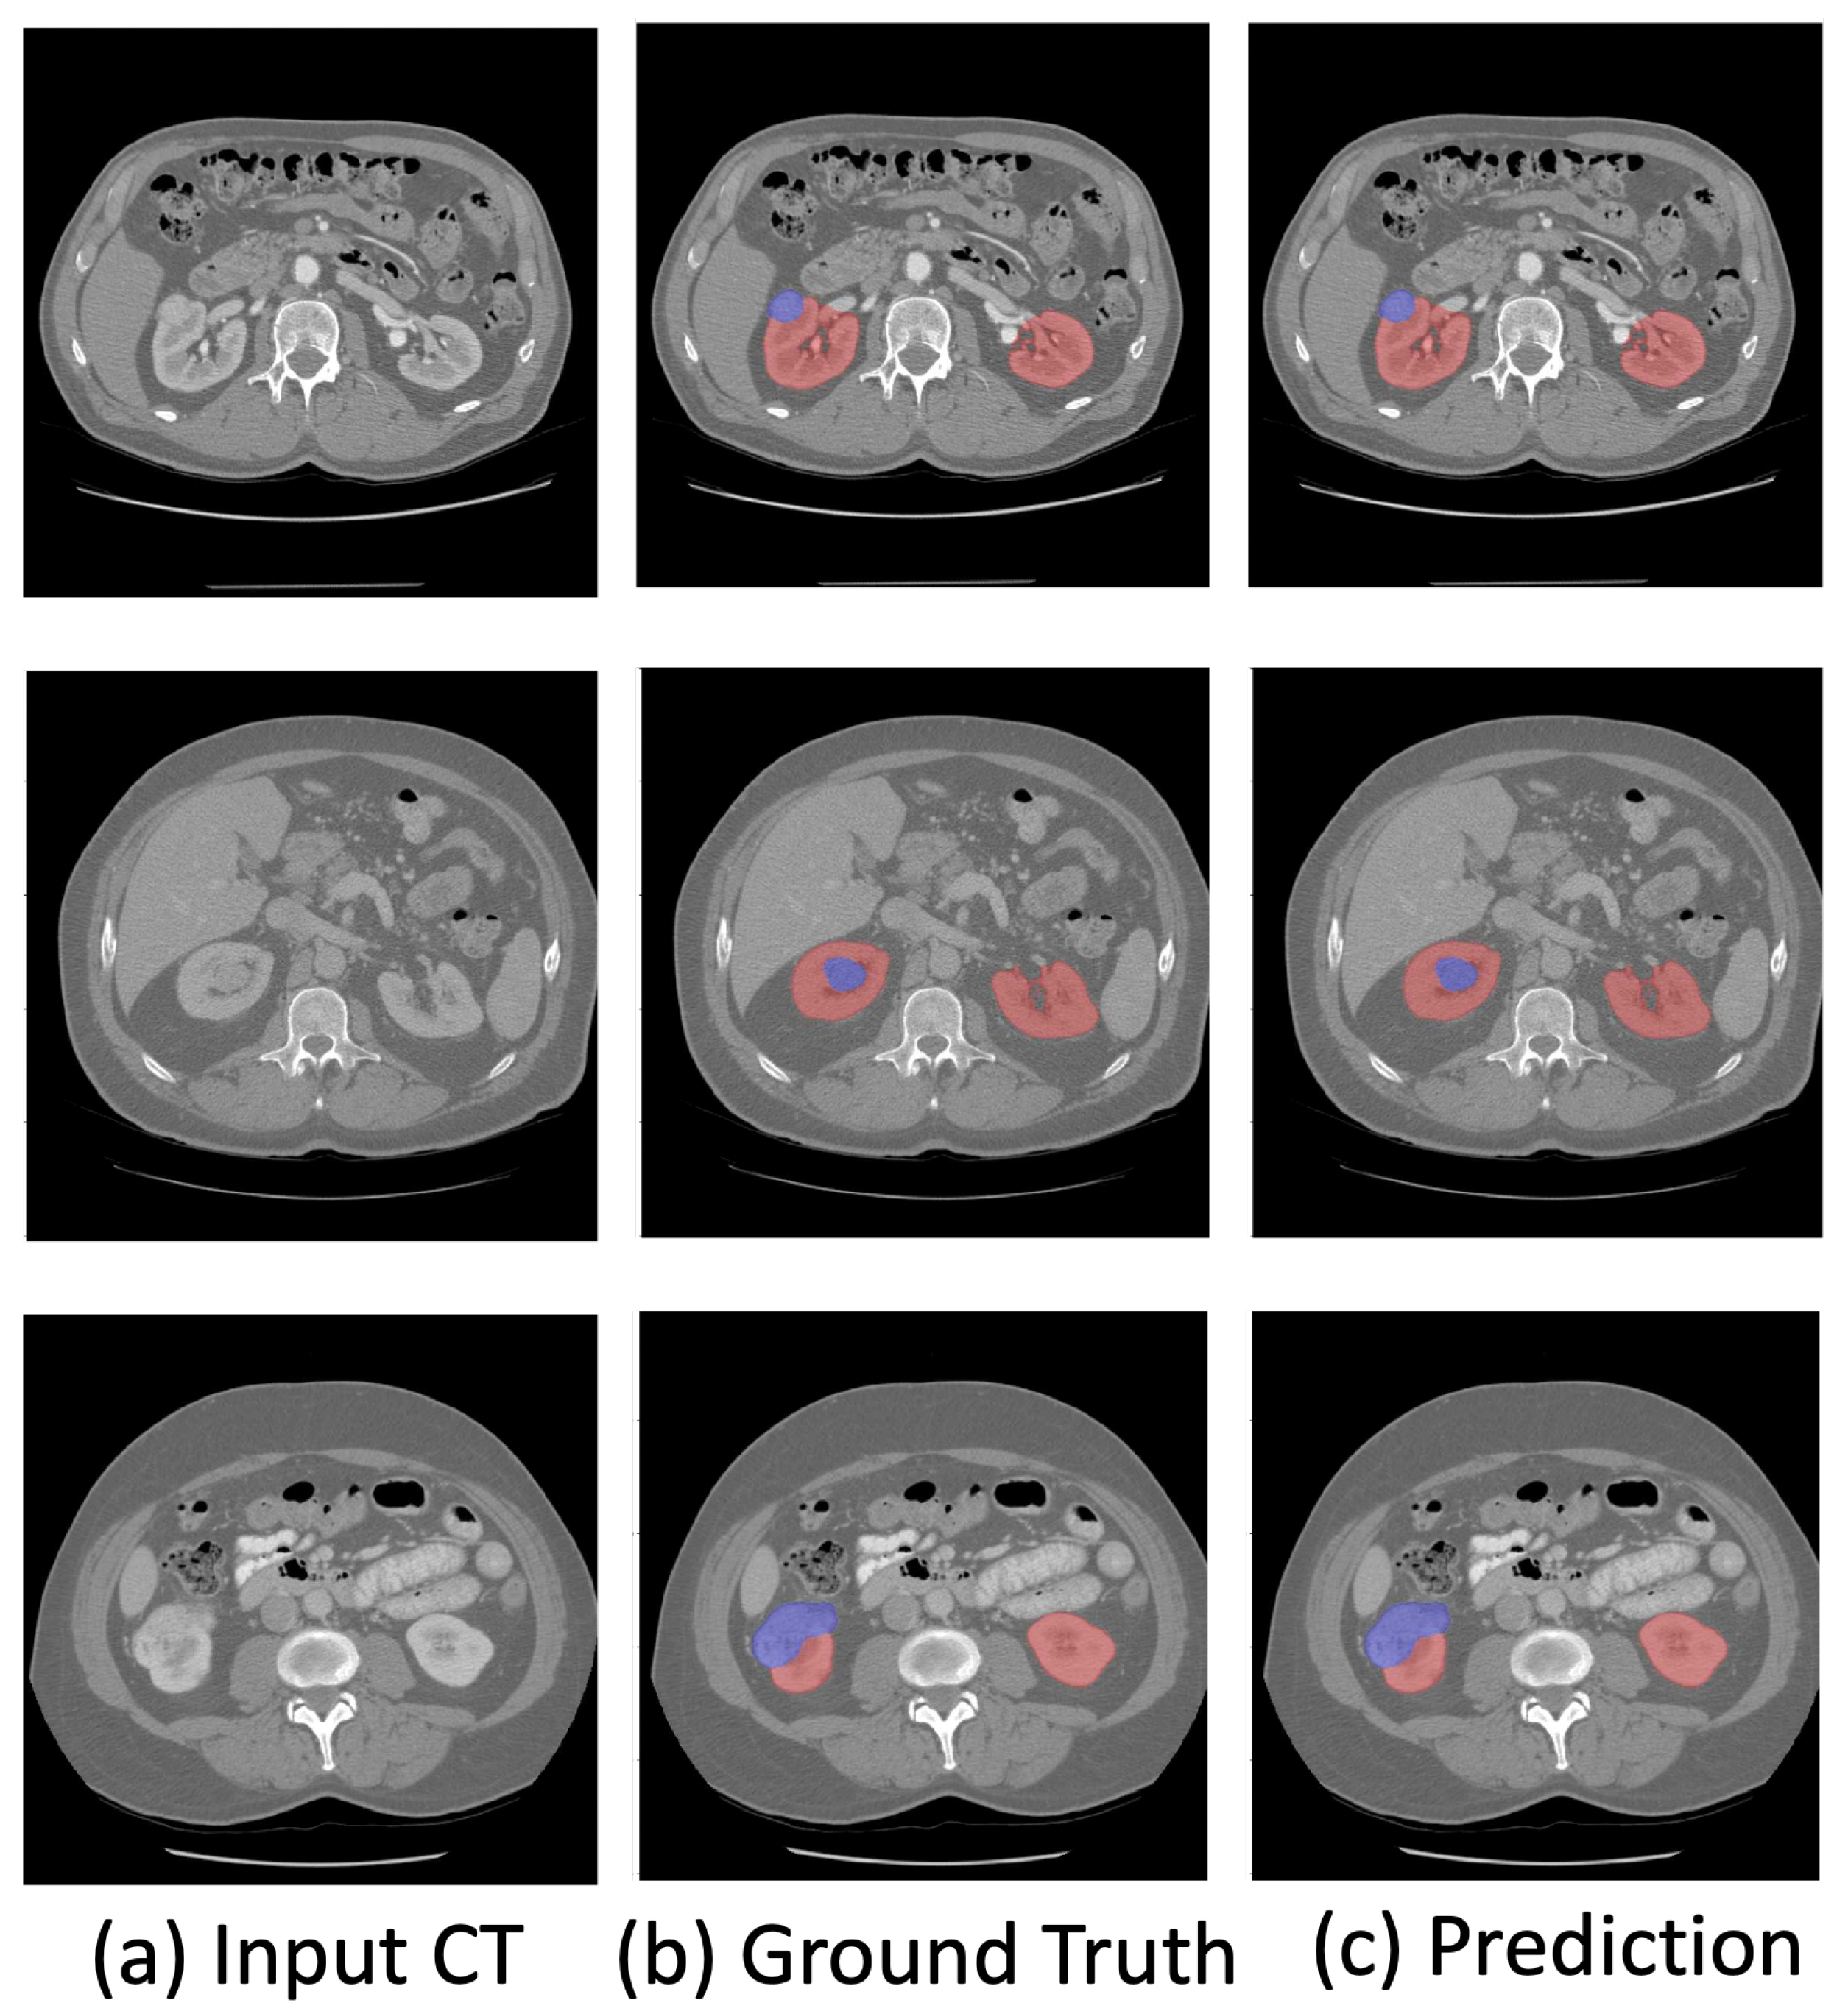

The visualization of the kidney region (red) and renal mass region (blue) overlaps with the original CT images shown in Figure 2. The visualization demonstrates the effectiveness of the proposed method in accurately segmenting the kidney and renal mass regions.

Figure 2.

Visualization of the predicted kidney (red) and renal mass (blue) segmentation.